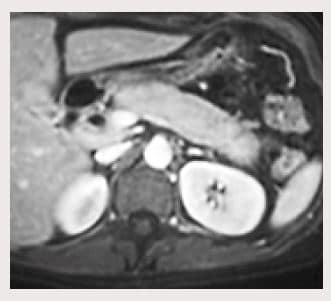

En los exámenes auxiliares que se muestran en la Tabla 3, se evidencia patrón colestásico con hiperbilirrubinemia a predominio directo. En el estudio con tomografía abdominal se observó colédoco dilatado en 1O mm, con aumento difuso del volumen del páncreas con captación tardía del contraste (Figura 1). En el estudio inmunológico se evidenció lgG4 en 610 u/L (VN: 1-200) y ANA 1/640 (Tabla 4). Se inició tratamiento con corticoide con respuesta favorable clínica y de laboratorio como se puede observar en la Tabla 3.

Figura 1. TAC abdominal con contraste; se evidencia un páncreas con agrandamiento de forma difusa con el diámetro a nivel de la cola de más de 2/3 el díametro transversal de la vértebra dorsal.

La imagen característica de la PAI, que se considera como nivel 1 de los criterios de CDCI (8) es un agrandamiento difuso del páncreas con realce en la fase tardía en la TC o RM abdominal y que puede tener o no el signo del “reborde en cápsula” (2). El aumento de tamaño difuso del páncreas es definido según los criterios de Haga como un diámetro de cabeza de páncreas de más de un diámetro transversal de la vértebra dorsal (3 cm) o un diámetro del cuerpo y de la cola de más de 2/3 del diámetro de la vértebra transversal (2 cm) esto puede encontrarse en 33% de los pacientes (9). El signo del “reborde en cápsula” es un signo especifico de PAI y se relaciona con los cambios fibróticos peripancreáticos, que se puede observar hasta en 30% de los pacientes (1,9).